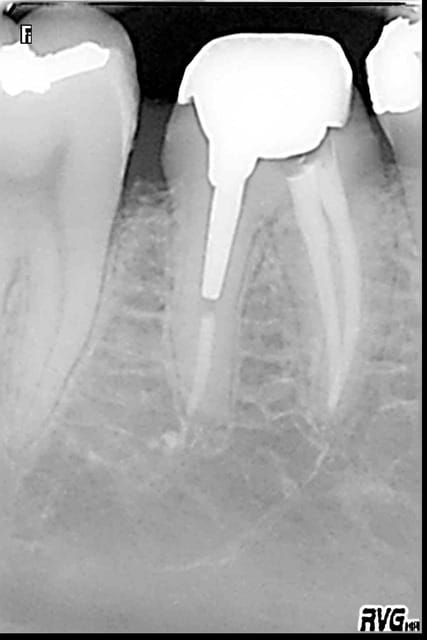

En général ca se termine comme ca.

R21 kcdjiv - Eugenol